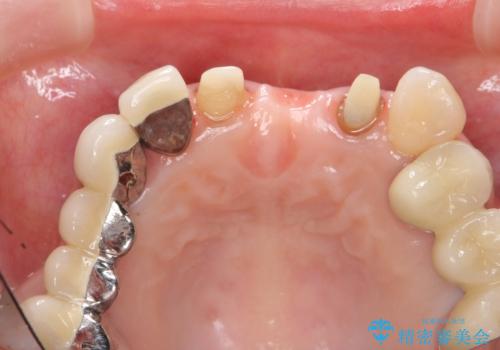

前歯ブリッジのやりかえ

- 前歯の審美障害、見た目の改善を希望され来院されました。

歯肉縁下カリエスも認められるため、挺出を行いセラミックブリッジを審美的に新製します。

- 47万円(仮歯×3・ファイバーコア×2・ジルコニアクラウン×3 歯の挺出)費用は治療当時の料金となります

虫歯が深くなった場合、挺出や歯周外科を行い歯周組織の状態を改善することでより安定した状態で予知性の高いセラミックブリッジを製作することが可能となります。